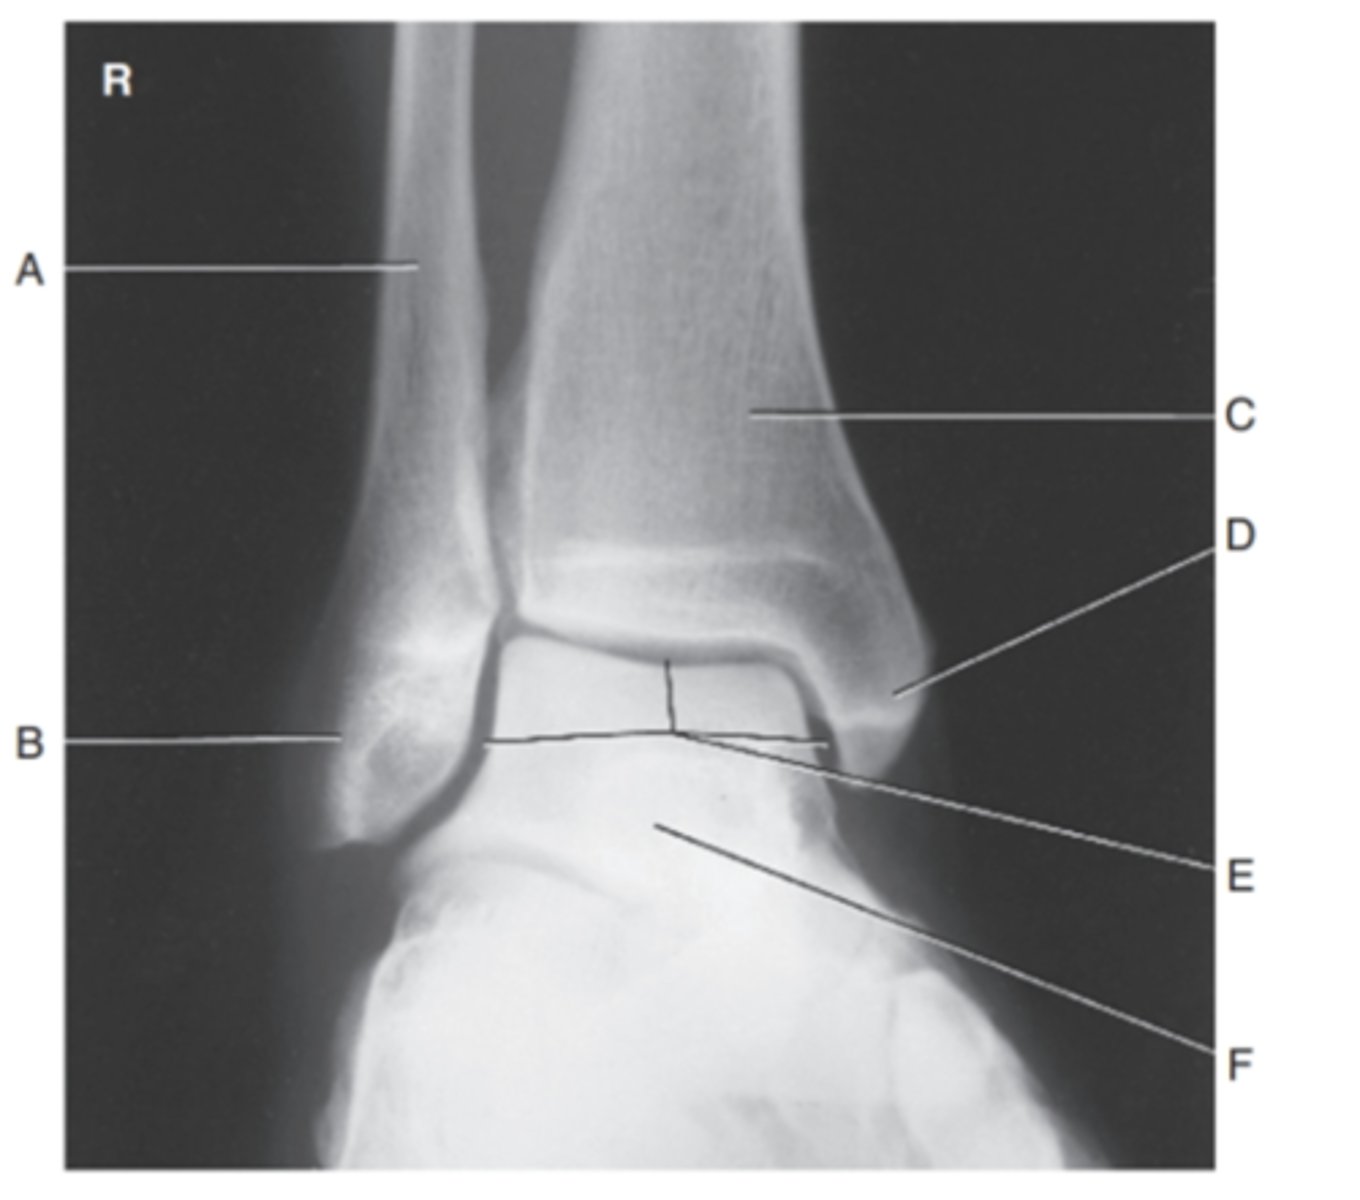

(LATERAL ANKLE) what is A?

tibia

what is B?

fibula

what is C?

tibiotalar joint

what is D?

talus

what is E?

navicular

what is F?

cuboid

what is G?

calcaneous